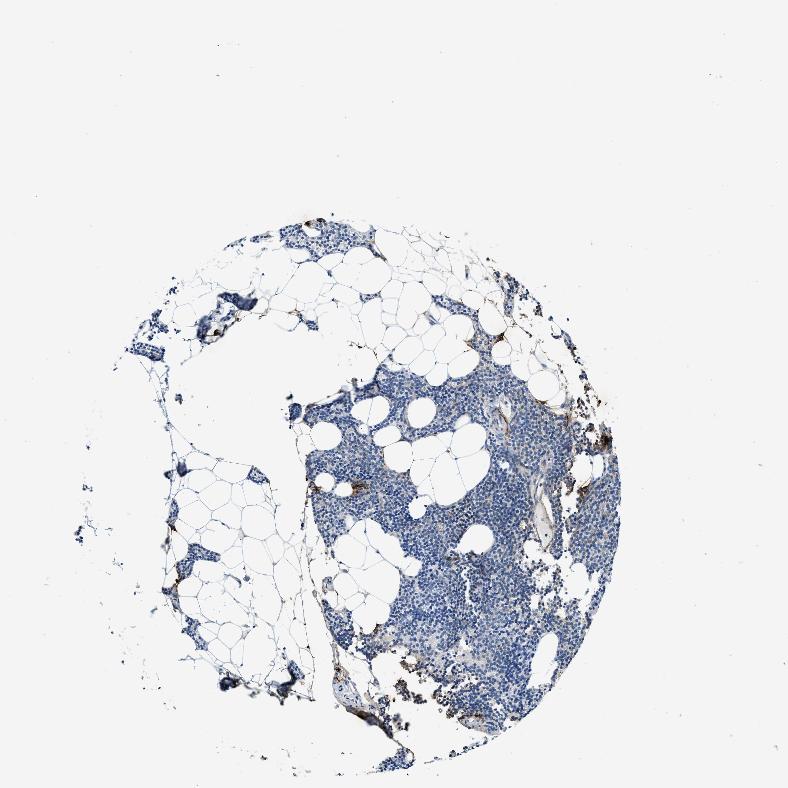

TISSUE PRIMARY DATA PARATHYROID GLAND Show tissue menu

Parathyroid gland

PARATHYROID GLAND - Expression summary

PARATHYROID GLAND - Antibody stainingi

Antibody staining in the annotated cell types in the current human tissue is reported as not detected, low, medium, or high, based on conventional immunohistochemistry profiling in selected tissues. This score is based on the combination of the staining intensity and fraction of stained cells.

Each image is clickable and will lead to virtual microscopy that enables deeper exploration of all samples and also displays staining intensity scores, fraction scores and subcellular localization as well as patient and tissue information for each sample.

Antibody HPA049153Antibody HPA049554Antibody CAB016369Antibody CAB022175

Glandular cells LowNot detectedNot detectedNot detected